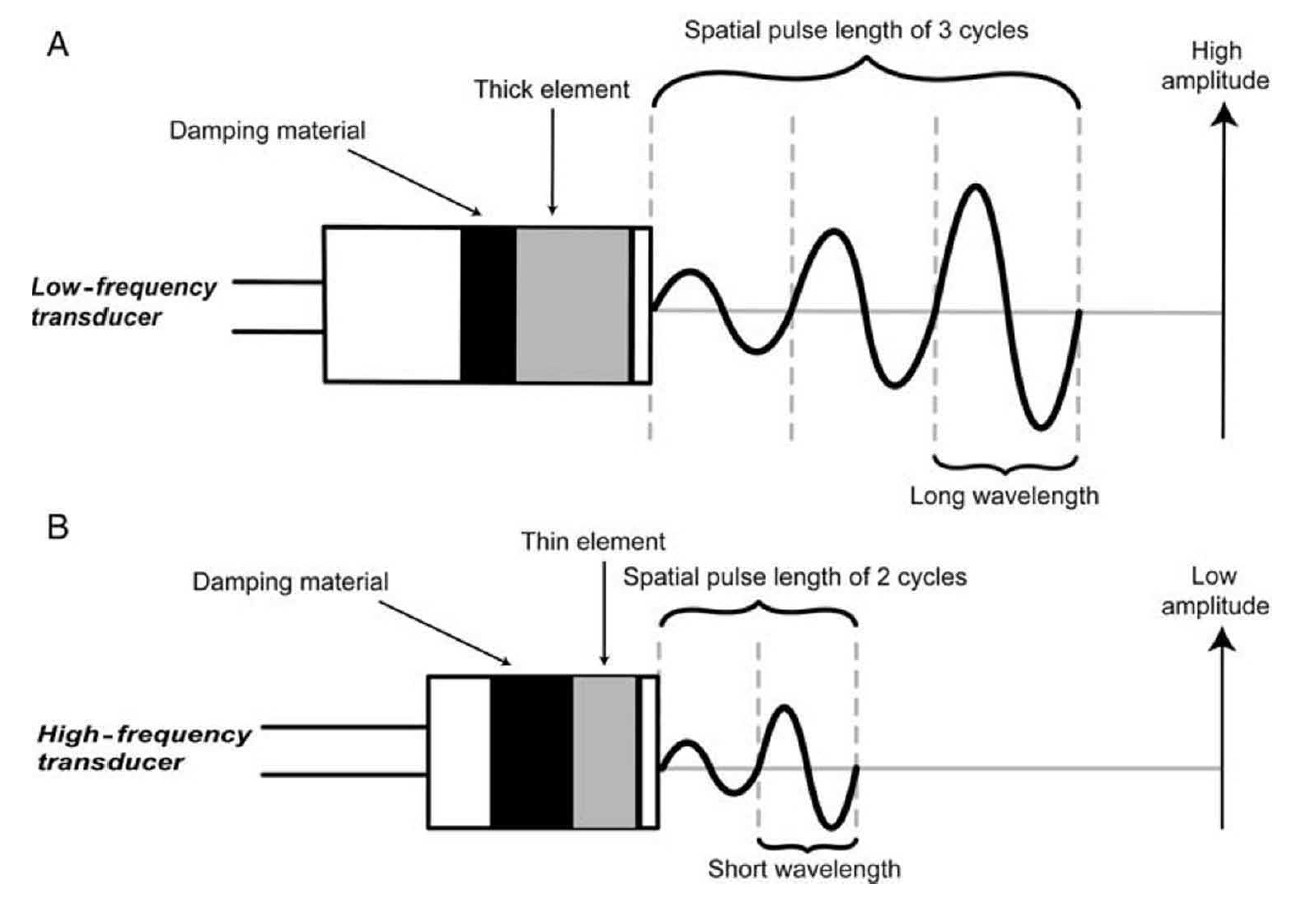

轴向(也称为纵向)分辨率是平行于超声波束方向的两个反射体之间可以区分的最小距离。在数学上,它等于空间脉冲长度的一半。空间脉冲长度是超声脉冲的周期数和波长的乘积(图 1A)。大多数脉冲由两个或三个周期组成,其数量由激励后压电元件的阻尼决定:高阻尼减少脉冲中的周期数,从而缩短空间脉冲长度(图 1B)。脉冲的波长由换能器的工作频率决定;高频换能器有薄的压电元件,可以产生短波长的脉冲(图 1B)。波长等于换能器中元件厚度的两倍。